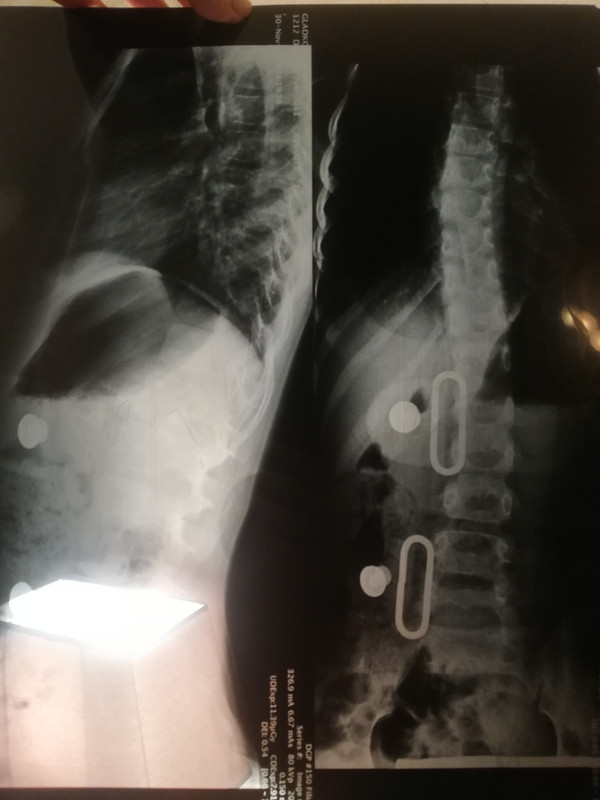

Сделали снимок, ужасно расстроена.

Снимок весь пересвеченный, дополнительно сделали боковую проекции, чтобы посмотреть кифоз, - дозу получили, а снимок не информативный, и сегмент не тот к тому же.

Гляньте, кто разбирается. Может, я драмматизирую ситуацию, и не так все плохо?

Рг1

Рг2

На снимке слева-июнь 2018,справа-свежий снимок. После июня было сильное ухудшение, сильный перекос, вырос большой горб, снимка у нас не было. В корсете с конца октября 20/24,без пелотов.